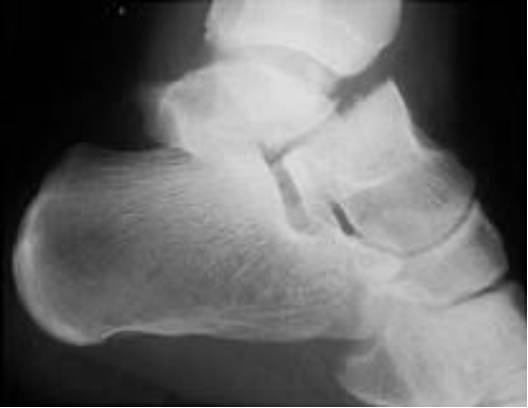

Chopart骨折脱位

即累及足的chopart关节的骨折脱位。Chopart关节为跗骨间关节(距舟关节、跟骰关节)。